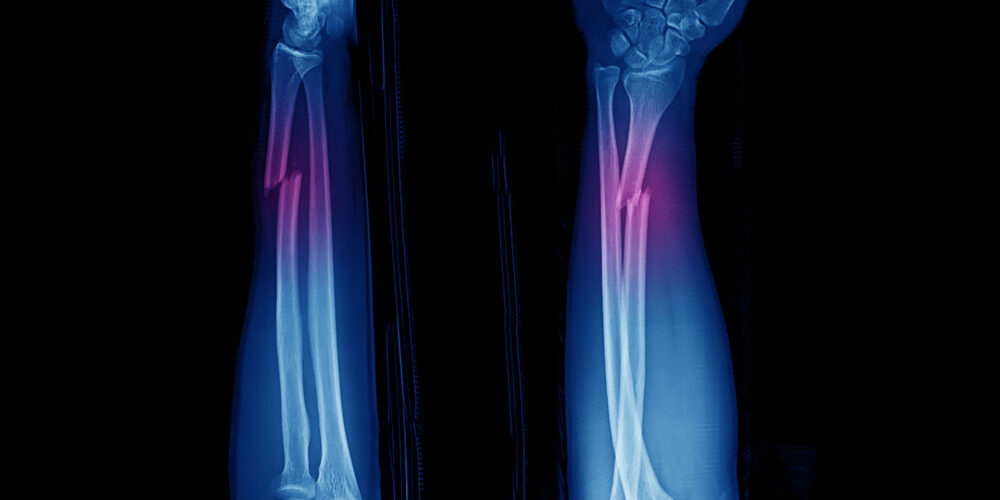

Κάταγμα Οστών

Αφορά τις κακώσεις οποιουδήποτε οστού, με αποτέλεσμα την ρήξη της συνέχειας του (κάταγμα ή σπάσιμο) δημιουργώντας την αδυναμία λειτουργίας του πάσχοντος σκέλους.

Διάγνωση

Κλινική και επιβεβαίωση με ακτινογραφία. Σε κάποιες περιπτώσεις απαιτείται και αξονική τομογραφία, όπως σε κατάγματα λεκάνης ή σπονδύλων.